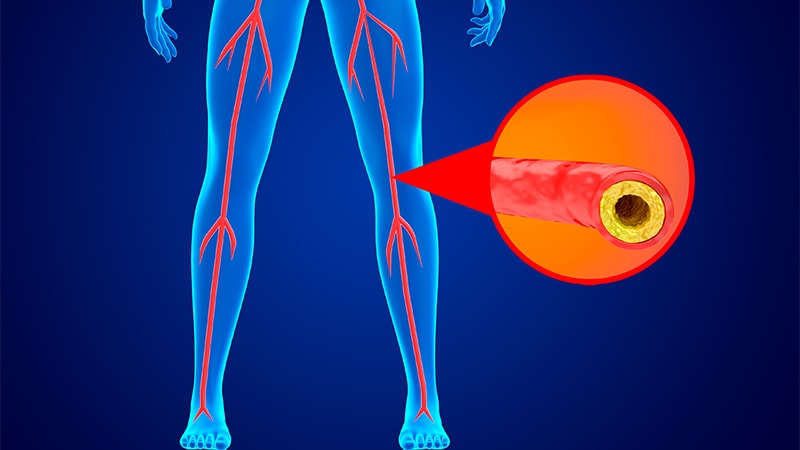

Изображения, связанные с атеросклерозом нижних конечностей и его лечением